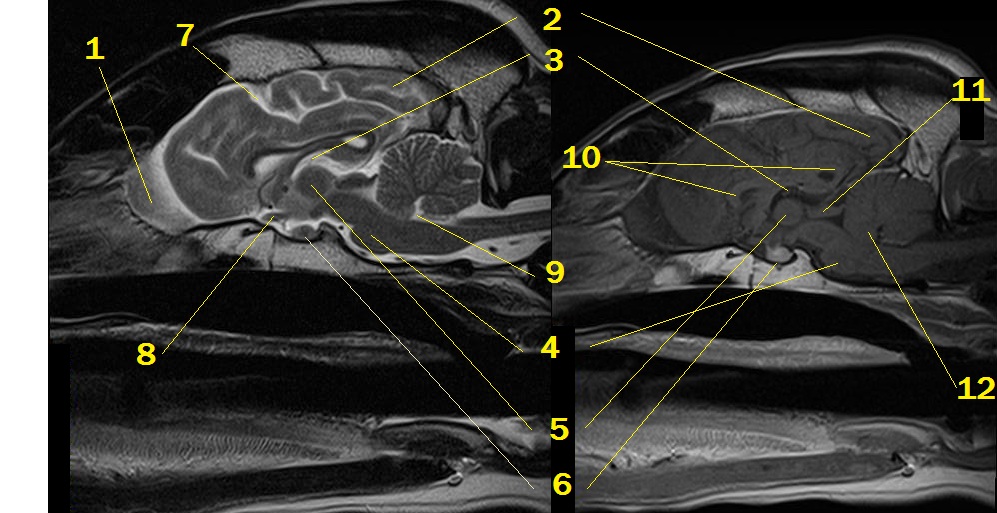

MRI anatomy 15

Q. Identify the structures labeled below:

A.

1. olfactory bulb

2. occipital lobe

3. 3rd ventricle

4. pons/ metencephalon

5. interthalamic adhesion

6. pituitary gland

7. cruciate sulcus

8. optic nerve near chiasm

9. 4th ventricle

10. hippocampus

11. rostral colliculus

12. lingua of the cerebellum